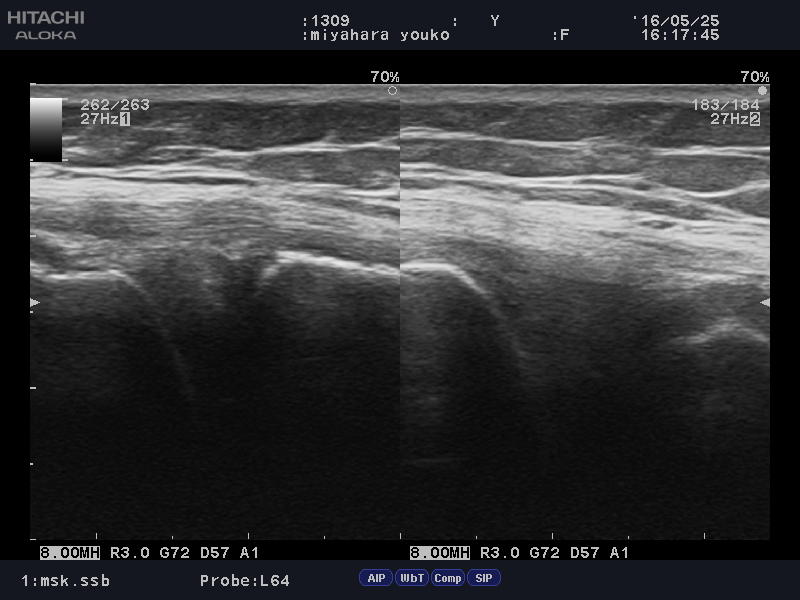

高所から椅子をふみ外し「膝の内側側副靭帯」を痛められた方。

Medial collateral ligament1.JPG